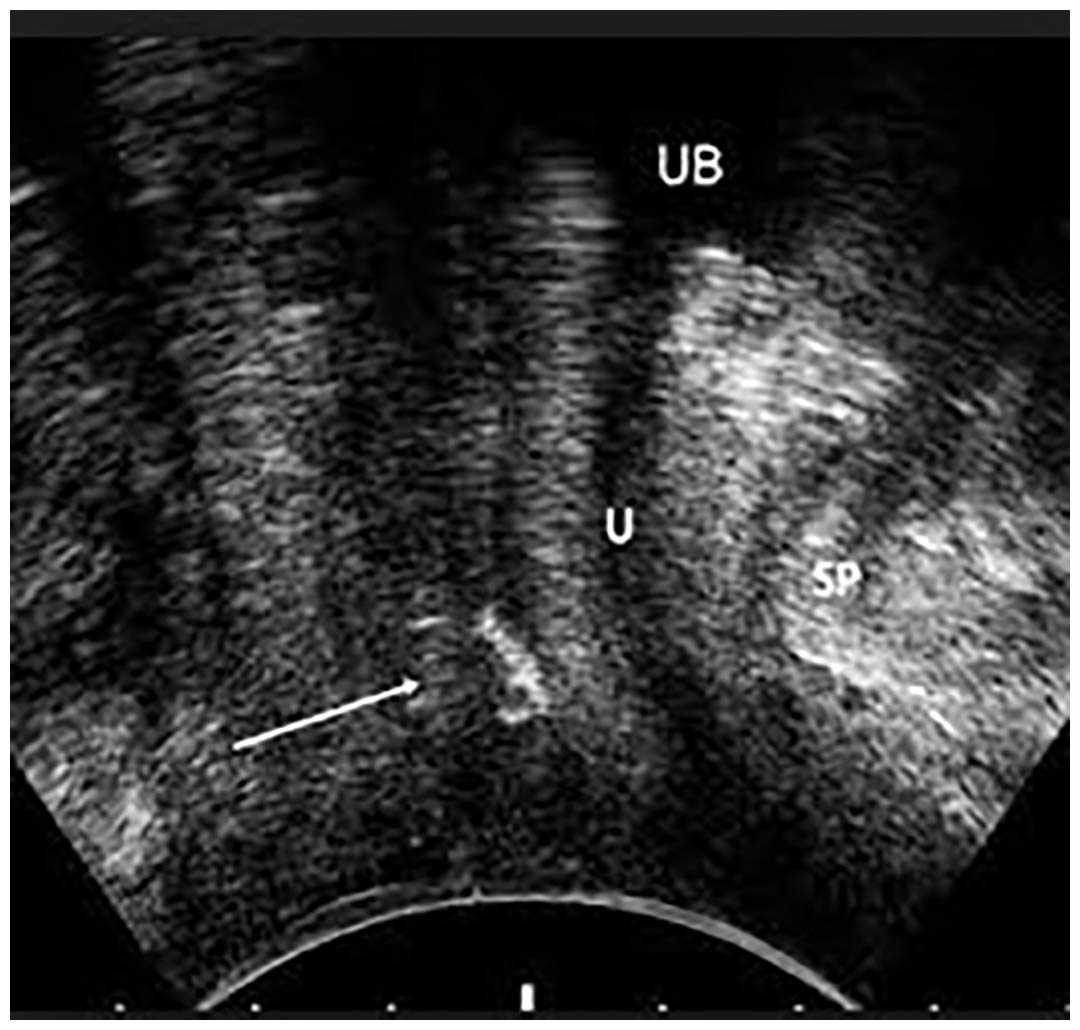

Among the 90 patients enrolled in our study, 48 patients underwent the classical surgical technique representing group 1 and 42 patients underwent the two para-median incisions representing group 2. Continence at 3 months in group 1 was 70.8%, 22.9% showed improvement in symptoms while only 3 cases representing 6% of case showed no improvement while in group 2, cure rate was 78.6%, 16.7% showed improvement in symptoms while only 2 cases representing 4% showed no improvement. 41.1% of cases showed tape migration either proximal or distal by trans-labial ultrasound in group 1 resulting in recurrence rate of 25% of cases, on the other hand no migration was noted in group 2 up to 12 months postoperative.

Trans-labial ultrasound was used to assess tape migration in the follow up period showing no migration of the tape for 1 year post-operative in our technique compared to a migration rate of 40 % in group 1 representing the standard technique that mainly occurred in the first 6 months, on evaluating the cases with tape migration and correlating with their clinical status, we noticed that 25% of the cases with tape migration showed recurrence in their symptoms in the standard technique especially to the distal urethra.

From our study, our new technique showed no tape migration compared to 40% migration rate in the standard technique, 25 % of the cases that showed recurrence of symptoms could be attributed to tape migration especially distal migration. Postoperative urgency was seen clinically correlated to tape placement in the proximal urethra and near the bladder neck.